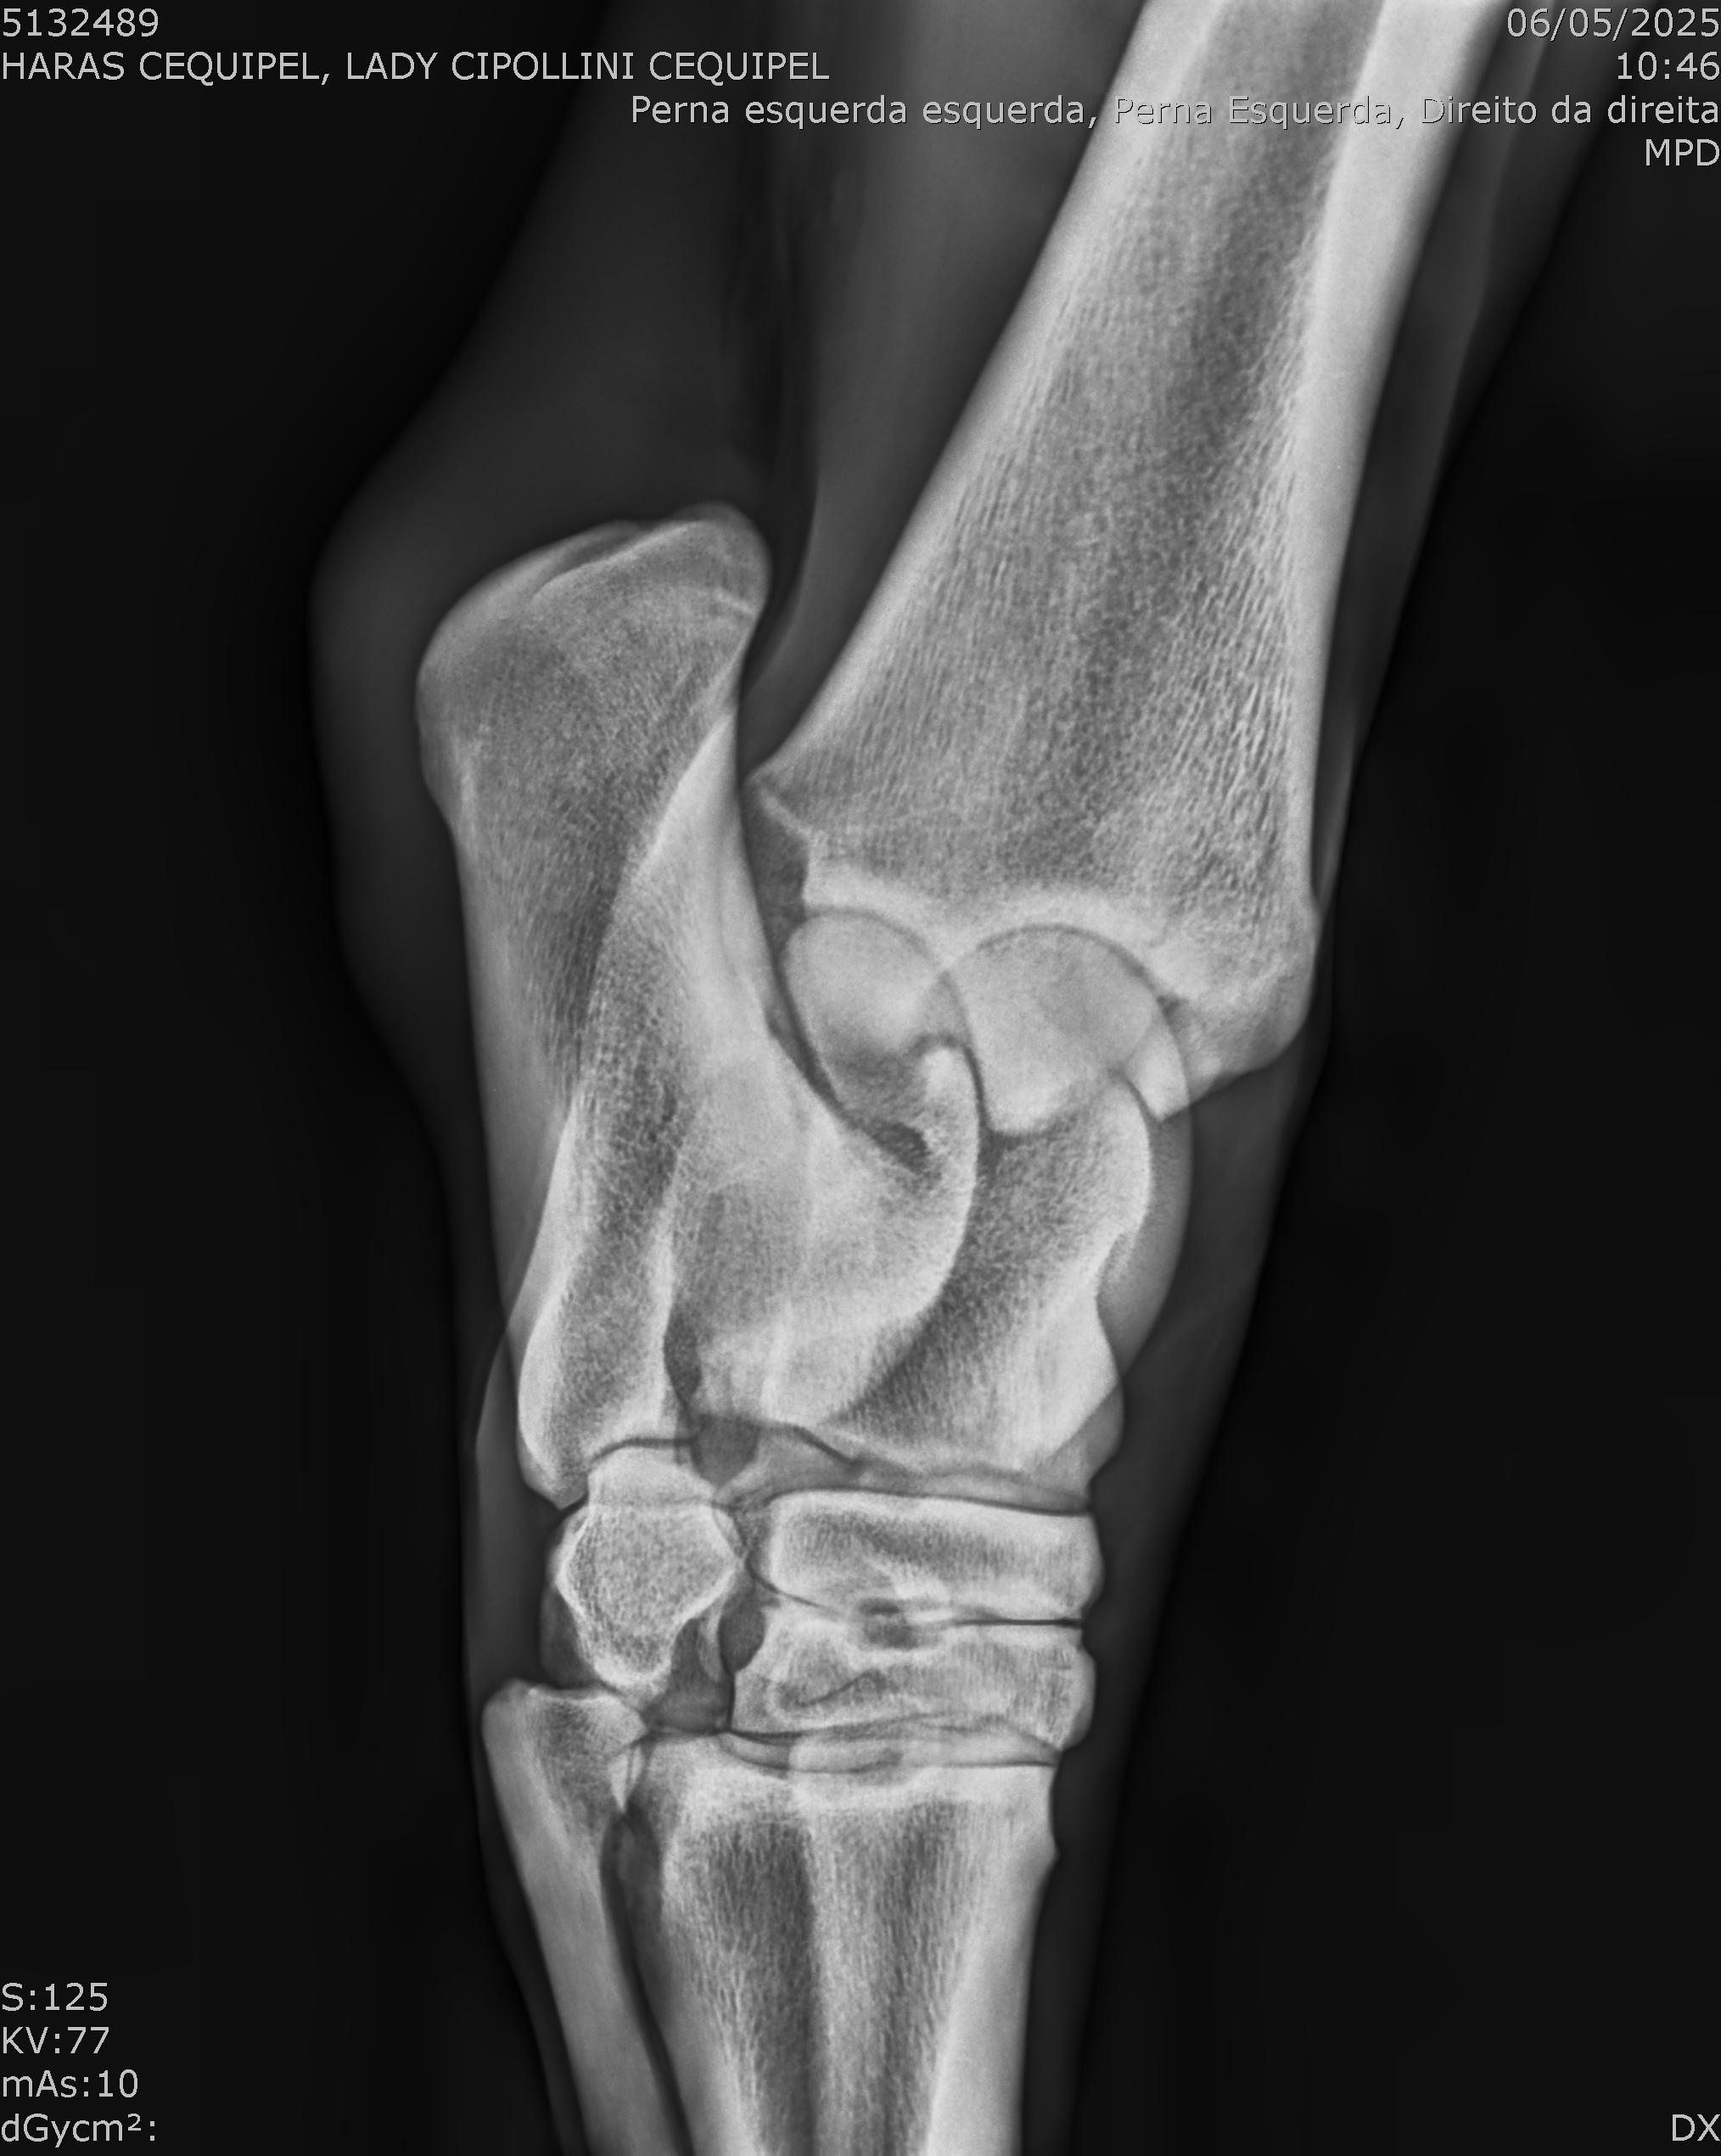

:: RAIOS-X DO LOTE